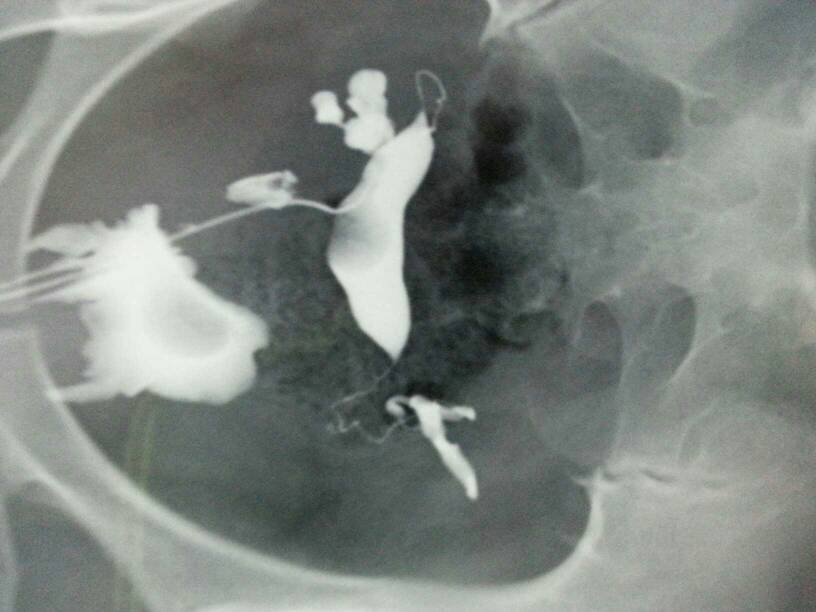

输卵管通而极不畅,有什么治疗方法吗?还是选择试管婴儿? 点击展开 匿名用户 2014-02-22 18:36 为您推荐: 其他回答 病情分析: 这个有输卵管通而不畅的情况,这样也不可以怀孕的,这个时间就算是能怀孕,宫外孕机会也很大的。 指导意见: 这个可以做通水或则是手术治疗,能完全疏通开的,也可以要孩子的,但如果疏通不开,就要考虑做试管了。 匿名用户 2014-02-22 18:39 相关问题 输卵管左侧通而不畅,是直接治疗还是做试管婴儿? 您好,我输卵管不通做试管婴儿,今天打促排卵针第十一天雌二醇一直下降,今天降到1110,这是什么原因? 我是输卵管通而不畅,请问有必要做试管婴儿吗?